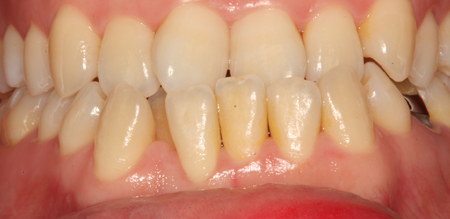

치주치료 전후사진

B

A

치주염 단계별 증상

건강한 상태

치아 주위의 잇몸이 핑크색을 띄며, 잇몸에서 피가 나지 않음.

스케일링을 6개월 ~ 1년 주기로 받고 올바른 칫솔질로 건강한 치주 조직을 유지

치은염 (초기~중기)

치아 주위의 잇몸이 붉게 부어 있으며, 칫솔질 등을 할 때 피가 남.

스케일링 주기의 조절이 필요할 수 있으며, 올바른 칫솔질을 시행하여야 함.

치주염 (중기~말기)

주기적으로 잇몸이 붓고 피가 나며, 욱씬하거나 우리한 통증이 나타남.

치주치료 및 정도에 따라 치주수술(잇몸수술)이 필요함. 향후 관리 정도에 따라 3~6개월 간격으로 내원하여 유지치료를 시행하여야 함.

치주염 (말기)

잇몸이 항상 부어 있으며, 이가

흔들리는 정도가 점점 심해짐.

치주치료가 필요하며, 정도에 따라 치아를 발치하여야 할 수 있음.